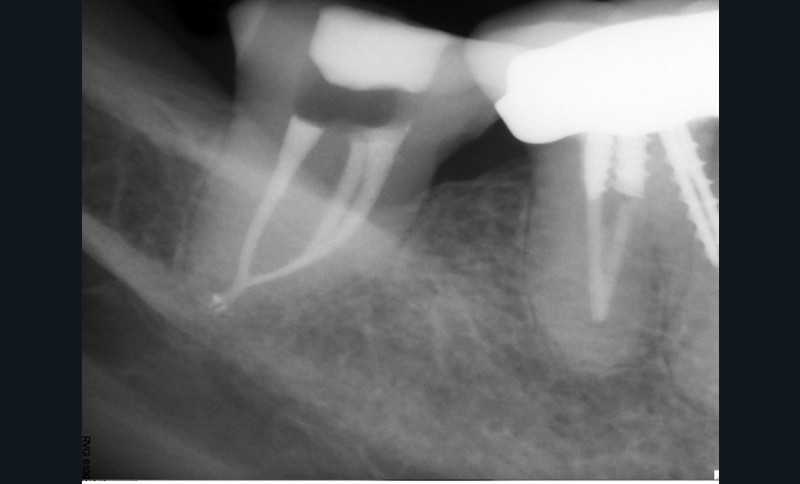

Endal, en 2011, montrait également, en utilisant le micro CT Scanner, l’insuffisance de nettoyage des isthmes inter-canalaires à nos techniques conventionnelles [19]. L’utilisation du laser Er:YAG devenait alors incontournable dans le nettoyage de ces isthmes et des zones non instrumentées (fig. 2 et 3).

Cette pénétration s’étend de la chambre pulpaire au réseau canalaire, isthmes, deltas apicaux et tubulis dentinaires. Il a été démontré que l’effet de cavitation pourrait permettre la destruction des bactéries à des profondeurs de 300 à 400 µm au sein des surfaces irradiées [20].

Si l’étude de Peters [18] nous montre que l’instrumentation laisse 35 % du volume canalaire non instrumenté, Ricucci et Siqueira montrent que la préparation physico-chimique n’élimine que partiellement les tissus nécrotiques à l’entrée des canaux latéraux, des isthmes et des ramifications apicales, en laissant des tissus enflammés et infectés, en association avec des lésions apicales [29] (fig. 4 et 5).